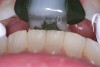

(3.) Example of initial distal contacts on an SRS orthotic. This is commonly seen when patients present for adjustment visits and is a positive sign that the condyles are seating in a more superior position.

Figure 3

At the delivery appointment, the splint must be equilibrated to allow for even, stable contacts and to ensure that there are no posterior interferences in excursive movements. As the joints stabilize and the condyles seat into the adapted centric posture, the splint will need to be further equilibrated. This will be evident when the patient begins to occlude first with the distal aspects of the splint (Figure 3). This is normal and a sign of positive treatment progress. Some patients will also experience the formation of a pseudo-disc over the head of the condyle. A pseudo-disc forms when undifferentiated mesenchymal cells in the joint space differentiate into chondrogenic and adipogenic cells and create a "callus" over the condylar head.10